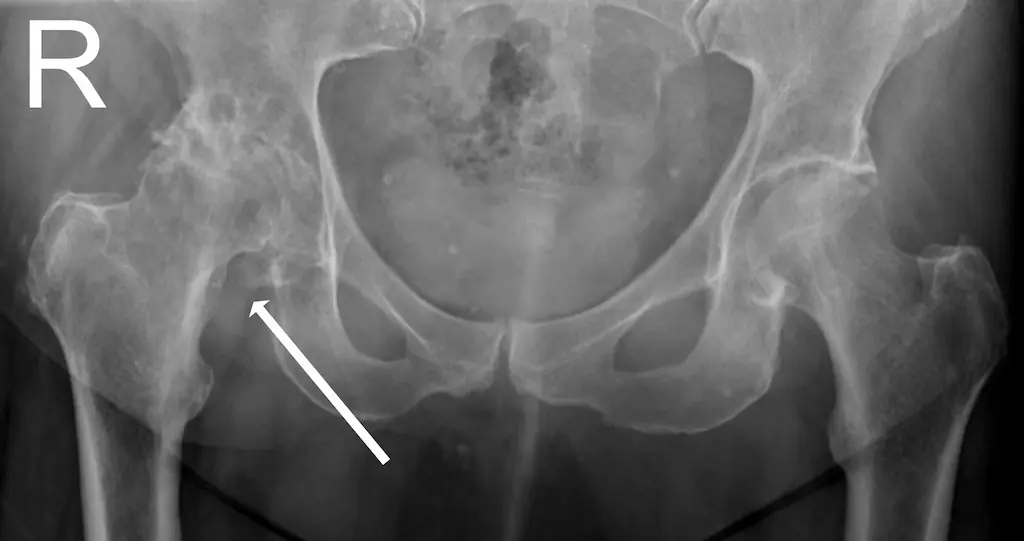

Xray showing hip OA

X-rays can show changes to the hip joint like above where the white arrow on the right hip looks different to the left hip.